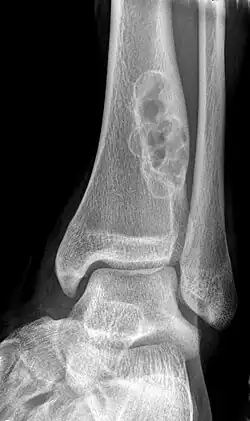

X-ray of nonossifying fibroma of distal tibia.

Diagnosis is by X-ray or MRI, usually when investigating a person for something else.[2] Medical imaging typically shows a well defined radiolucent lesion, with a distinct multilocular appearance, sometimes looking like bubbles.[2] It is usually around 1–2 cm in size, but be as large as 7 cm.[3] They consist of foci consist of collagen rich connective tissue, fibroblasts, histiocytes and osteoclasts.[2] Usually no treatment is required.[1] Surgical curettage and bone grafting may be required if it is large.[3]

It is usually diagnosed by x-ray or MRI, when investigating another problem.[1] The tumor presents as a well defined radiolucent lesion, with a distinct multilocular appearance, sometimes looking like a "soap bubble".[5] If small and no symptoms, then biopsy is not needed.[1]